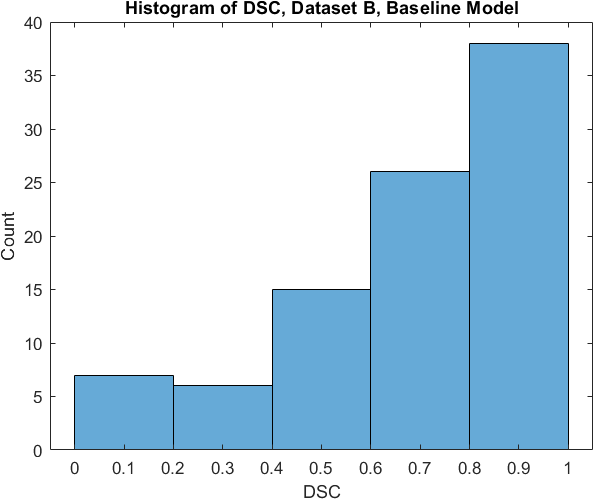

Qualitative prediction results of the two proposed models (baseline nnU-Net and nnU-Net with coordinate convolutions) on the two datasets are shown in Figure 2. Tables 1 and 2 summarise the quantitative performances in terms of DSC and area statistics. Histograms of the DSC values are shown in Figure 3. The median DSCs between the manual segmentations on the subsets of 10 images (i.e. the estimates of inter-observer variability) are also shown in Table 1.

It can be seen that, despite having fewer images, the baseline model for Dataset A obtained a higher median DSC than the model for Dataset B. For Dataset A the coordinate convolution model improved the DSC and reduced the area error and bias. In two-tailed Wilcoxon signed rank tests (0.05 significance) the difference between the baseline DSC and that of the coordinate convolution model was found to be statistically significant for Dataset A () but there was no statistically significant difference for Dataset B (). Interestingly, for both Dataset A and Dataset B, both the baseline and coordinate convolution models performed better than the estimate of inter-observer variability. However, we note that the inter-observer variability is quite high (i.e. median DSCs of 0.78 and 0.71), likely reflecting the difficulty and partly subjective nature of the effusion segmentation task. Therefore, it seems likely that the deep learning models are learning to segment effusion in the style of the main observer, which may not always be consistent with the second observer. In addition, the histograms shown in Figure 3 suggest that there are a significant number of failure cases in the outputs of both models (although fewer for the coordinate convolution model for Dataset A), again reflecting the difficulty of the task.